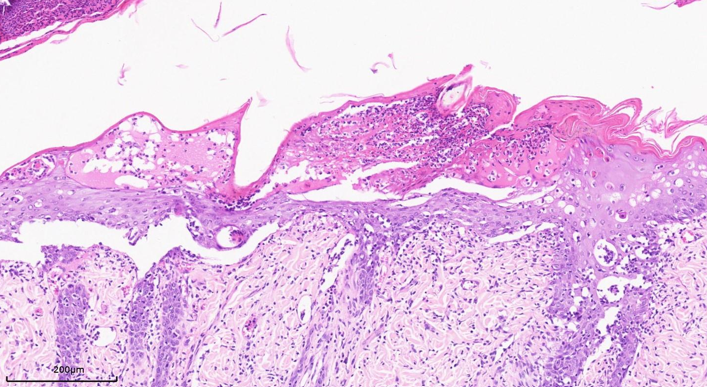

银屑病是一种常见的慢性复发性炎症性皮肤病,以表皮角质形成细胞过度增生伴角化不全,真皮微血管迂曲扩张及炎症细胞浸润为主要病理生理学特征。

皮肤角质层角化(蓝色→);表皮棘层增厚(绿色→),表皮小脓肿(黑色→);真皮层炎细胞浸润(红色→

毛细血管增生(黄色→

银屑病病理评分标准(表皮增生,角化过度,Munro微脓肿,炎症浸润,真皮乳头水肿,血管增生/扩张)

模型组-200x  真皮乳头水肿(黑色→),血管增生(蓝色→),炎症聚集(黄色→

对照组-800x  表皮厚度(32.2μM)                                   模型组-800x 表皮厚度增厚(134.9μM)

模型组-200x:表皮Munro微脓肿                                       模型组-200x:表皮层角质增厚

中性粒细胞聚集层,伴有坏死和细胞碎片                            角化不全,角质层增厚